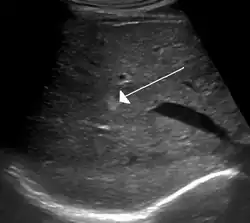

Ultrasound of hemangioma in the liver

On ultrasound, cavernous haemangiomas in liver appear as homogenous, hyperechoic lesions with posterior acoustic enhancement. On CT or MRI scans, it shows peripheral globular/nodular enhancement in the arterial phase, with portions of attenuation of enhancing areas. In the portal venous phase, it shows progressive centripetal enhancement. In delayed phase, it shows retention of contrast. It shows a high signal on T2 weighted images.[24]